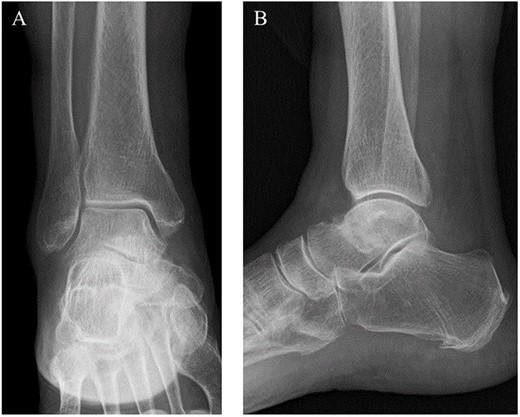

A 76-year-old female, who worked as a cleaner, complained of pain in her right ankle when going downstairs while working. She had medical history of only osteoporosis and had taking daily active vitamin D for >10 years. She was given conservative treatment for 1 month at a local clinic, however, her ankle pain persisted and so she visited our clinic. Physical examinations revealed tenderness and swelling at the anterior aspect of the ankle. Plain radiographs showed no obvious abnormal findings (Fig. 1). Magnetic resonance imaging (MRI) revealed a low signal linear line in the talar neck and a bone marrow edema around the line (Fig. 2). Non-contrast computed tomography (CT) demonstrated an obvious fracture line in the talar neck, however, the bone fragment was not displaced (Fig. 3). Based on medical histories, clinical and radiological findings, we diagnosed her with a fragility fracture of the talar neck associated with osteoporosis. Because the patient was elderly and it was difficult to treat using a prolonged non-weightbearing cast, we applied operative treatment to allow early rehabilitation. The operation was performed under spinal anesthesia in a prone position with an air tourniquet and a fluoroscopy. The posteromedial and posterolateral portals were created according to van Dijk et al. [10]. First, the posterior aspect of the talus was observed using a 4.0-mm diameter 30° arthroscope, and soft tissues around the talus (including synovium and adipose tissues) were removed with a 3.5-mm diameter motorized shaver. After confirming the posterior part of the talar body and the FHL, two 1.6-mm diameter guidewires were parallelly inserted from the posterior part of the talar body to the talar head by hindfoot endoscopy and fluoroscopy (Fig. 4A), and two cannulated 4.5-mm diameter double-threaded screws (Double Thread Screw, Meira, Nagoya, Japan) were inserted through the guidewires (Fig. 4B). The wound was sutured, and the operation was concluded (Fig. 5). Active range of motion exercises were allowed immediately after surgery, and a non-weightbearing short leg splint was worn for 1 week. Partial-weight bearing was permitted at 2 weeks and full-weight bearing was permitted at 4 weeks post-operatively. In addition, daily injections of teriparatide (Forteo, Eli Lilly and Company, Indianapolis, IN, USA) were introduced 2 weeks post-operatively. Eight weeks after the operation, the patient was able to return to work without pain or functional impairment. One year postsurgery, the patient was still working as a cleaner without any symptoms or complications.

MRI revealed a low signal linear line in the talar neck and a bone marrow edema around the line on a fat-suppressed T2-weighted (FS-T2) image.